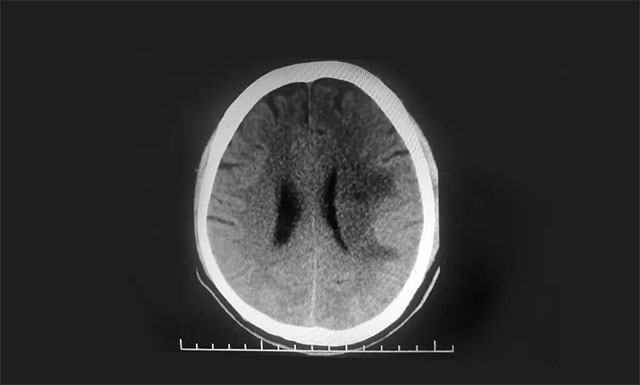

▲ 術(shù)后CT復(fù)查,出血基本已吸收